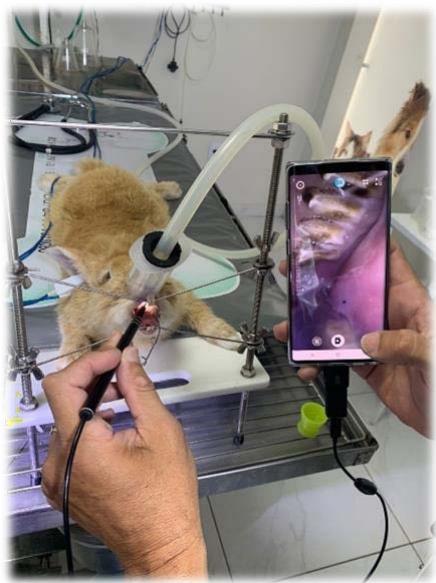

No dia 13 de Setembro de 2021 no Hospital Veterinário Jefferson Ricardo, situado em João Pessoa, Paraíba, o paciente foi operado. O tratamento consistiu na redução da coroa clínicados incisivos por meio de odontosecção com disco de corte diamantado (Fig. 11 e 12) e dos pré molares e molares usando a peça reta com uma broca carbide esférica ${ \mathsf { n } } ^ { \circ } \ 8,$ buscando a oclusão correta dos incisivos, que acontece quando os incisivos inferiores se encontram entre os incisivos superiores anteriores e posteriores e uma angulação próxima dos $10 ^ { \circ }$ para os pré molares e molares, que é o preconizado na literatura VESTRAETE, Frank (2005). Essa verificação foi feitapor meio do registro fotográfico utilizando-se uma micro câmera anexada ao celular e também uma câmera digital (Fig. 13, 14 e 15 a,b,c).

Fig. 13: Uso da Micro câmera para conferência do desgaste oclusal

Fonte: Arquivo pessoal do autor Fig. 14: Uso da câmera digital para oregistro e documentação do caso